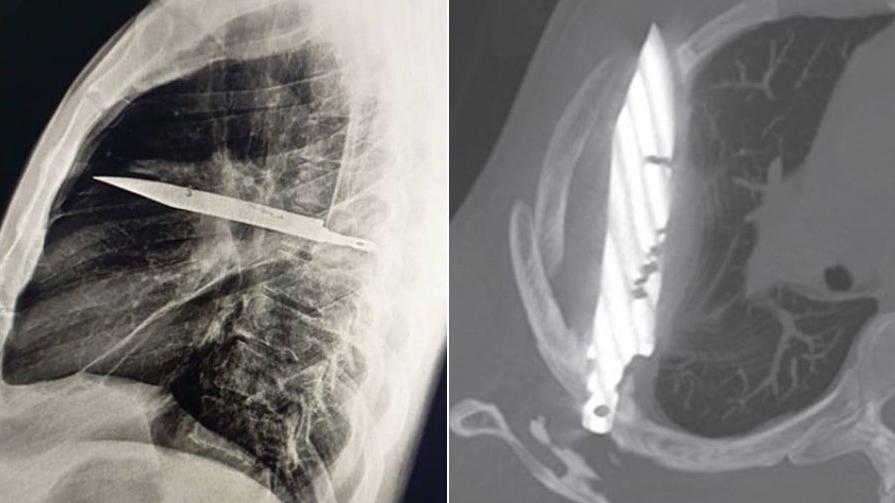

• 胸部X光影像可見,有一把刀插在男病人胸腔內。(互聯網)

坦桑尼亞男子乳頭疼痛流膿 X光檢查驚見胸腔插刀 長達8年